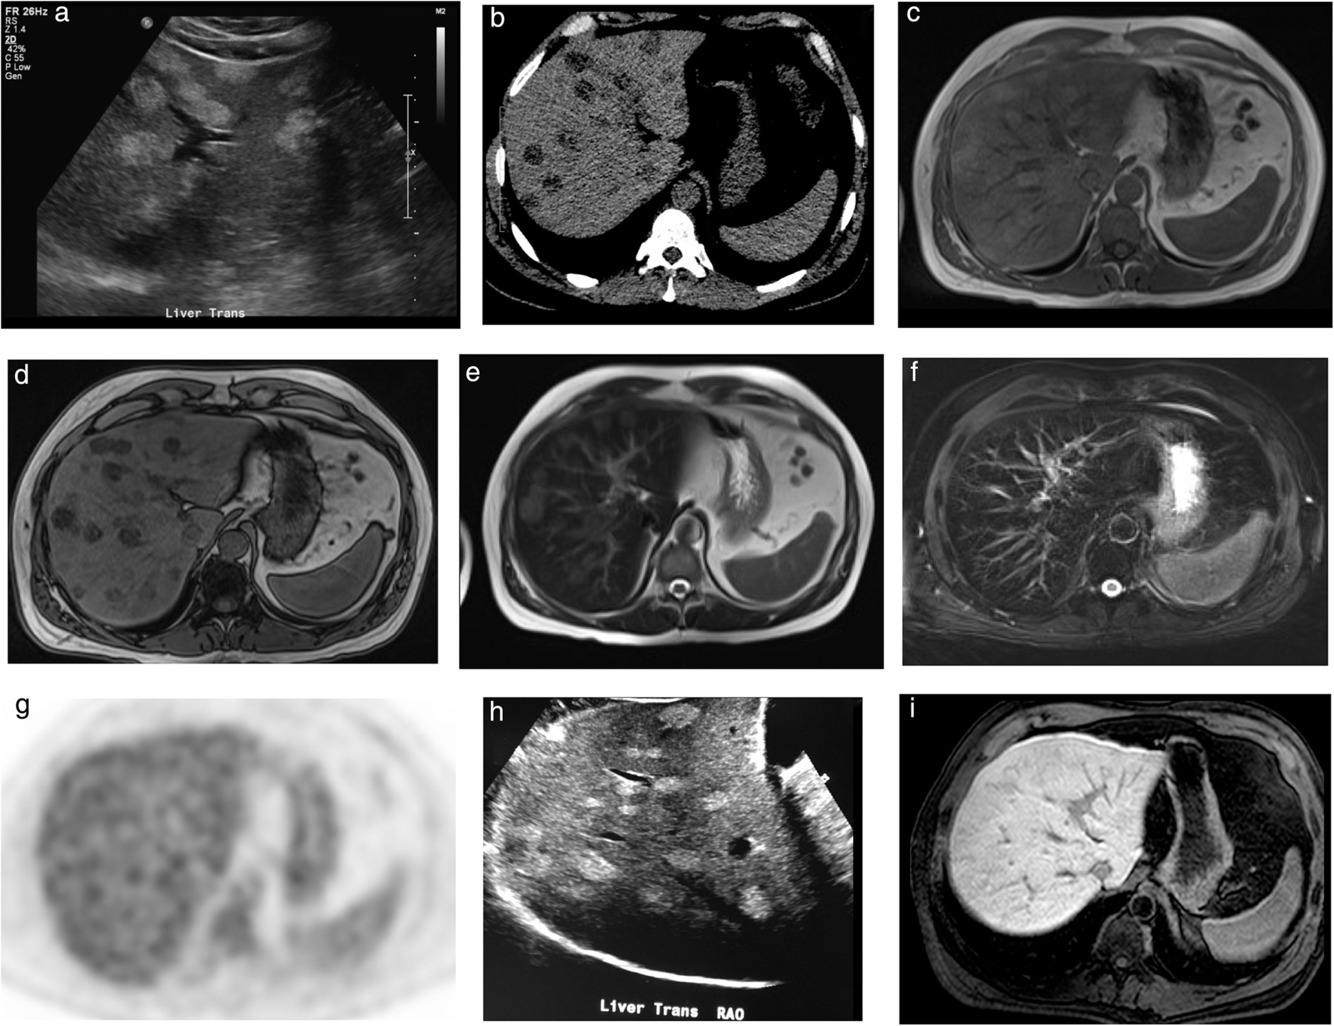

# Abdome: doença hepática difusa HD?

Telangiectasia Hemorrágica Hereditária ou Síndrome de Osler-Weber-Rendu (THH-OWR). ## Footnote Malformações vasculares intra-hepáticas (e pulmonares), com artérias ectasiadas e tortuosas, shunts; realce venoso precoce .

Hepatite aguda (HepA). ## Footnote Edema periportal, líquido livre e **importante** espessamento parietal da vesícula biliar (seta). Geralmente também há hepatomegalia.

Esquistossomose. ## Footnote Distorção arquitetural (aparência em casco de tartaruga) bandas fibrosas periportais e fissuras alargadas; Calcificação capsular - setsa (paralela ou perpendicular à superfície do fígado) característica. Hipertensão portal.

Colangite esclerosante primária (CEP). ## Footnote Irregularidade dos ductos biliares, com áreas de estenose alternando com dilatações. Na TC sinais de fibrose (doença avançada).

# Abdome: doença hepática difusa **V ou F?** Na imagem temos o aspecto de atrofia do fígado periférico e hipertrofia central (pseudotumor do lobo caudado), característico da CEP em estágio avançado.

Verdadeiro.